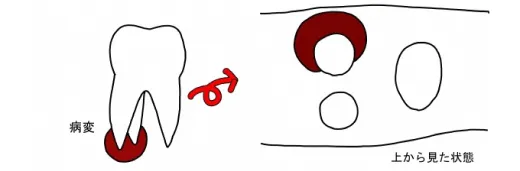

コーンビームCT導入の利点

今までのレントゲン撮影では、画像を平面として診断していたので画像の重なりから診断には限界があり、また治療にも無駄が生じていました。たとえば、根の先に病気があってもどの根に病気があるのかわからないためすべての根の治療が必要でした。また、歯周炎で骨が溶けていても、立体的に外側が溶けているのか内側が溶けているのかは判断が難しいことがありました。 しかし、CT撮影をすれば画像を通して瞬時に診断か可能です。従来のレントゲンでは立体を把握するために、わざと画像をずらして2枚撮影し診断しなければならなかったモノが、一度の撮影ですむ利点があります。診断が簡便正確にできれば、治療に要する時間も短縮でき、また精度も向上します。治療成績も上がると考えています。 また、不幸にして歯が持たない状態になっている場合でも、その判断に客観性が生まれ、不必要な治療に時間を割く必要がありません。もちろん、すべてがわかるという訳ではありませんので、それに対する知識や経験の蓄積が必要なのはいうまでもありません。 更に、持たない歯を抜いた場合、予想される骨の吸収量をより正確に予想することも可能なため、その部分を補う場合に必要な治療オプションを事前に提示することも可能になります。たとえば、インプラントを応用する場合でも、即時に行えるか、準備が必要な状態なのかを事前に判断することが可能になります。

CT撮影では何が分かるのか?

1.重なり合って分からなかった病変の原因を特定できる

2.骨が溶けている範囲が骨に囲まれているか否かを判別できる

3.歯の根が折れているのかどうかを骨の溶け方から推察できる

4.根の先が神経や上顎洞からどのくらい離れているのか診断できる

5.埋伏している歯がどこにあるか正確に分析できる

上記のようなことが、CTでは分かります。また一方、CT上で分からないものは、次のようなことです。

- ・ 金属などX線が乱反射して診断の障害になる。または診断不能になることがある。

- ・ 根の破折は破片が分離していないと正確には判断しにくい。

- ・ 骨の硬さによっては見やすい画像が撮れないことがある。

CTも画像で診断するモノなので、うまく写っていなければ診断も難しく、術者の経験と勘が要求されることもあるということです。